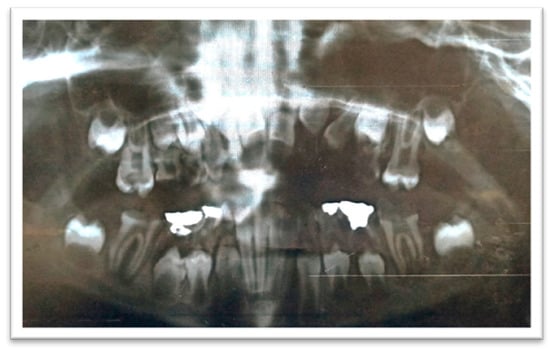

2. Case Report

| Special health needs Visible cavitations Enamel demineralization or hypomineralization Lowsocioeconomic status Insufficient oral hygiene measured with the aid of a plaque score High sugar intake measured by a dietary chart Medications that impair saliva flow (Tegretol) Poor toothbrushing performed only on days of dental treatment |